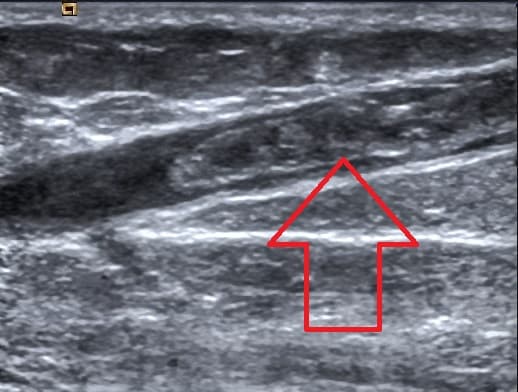

Superficial vein thrombosis (SVT) is a blood clot formed in a superficial vein, a vein near the surface of the body. Usually there is thrombophlebitis, which is an inflammatory reaction around a thrombosed vein, presenting as a painful induration (thickening of the skin) with redness. SVT itself has limited significance (in terms of direct morbidity and mortality) when compared to a deep vein thrombosis (DVT), which occurs deeper in the body at the deep venous system level. However, SVT can lead to serious complications (as well as signal other serious problems, such as genetic mutations that increase one's risk for clotting), and is therefore no longer regarded as a benign condition. If the blood clot is too near the saphenofemoral junction there is a higher risk of pulmonary embolism, a potentially life-threatening complication. SVT has risk factors similar to those for other thrombotic conditions and can arise from a variety of causes. Diagnosis is often based on symptoms. There are multiple possible treatments, with the goal of providing symptomatic relief and preventing complications. SVT is recognized by the presence of pain, warmth, redness, and tenderness over a superficial vein. The SVT may present as a "cord-like" structure upon palpation. The affected vein may be hard along its entire length. SVTs tend to involve the legs, though they can affect any superficial vein (e.g. those in the arms). SVT in the lower extremities can lead to a dangerous complication in which the clot travels to the lungs, called pulmonary embolism (PE). This is because lower limb SVTs can migrate from superficial veins into deeper veins. In a French population, the percent of people with SVTs that also suffered from PEs was 4.7%. In the same population, deep vein thrombosis (DVT) was found in 24.6% of people with SVTs. However, because superficial veins lack muscular support, any clots that form are far less likely to be squeezed by muscle contraction, dislodged, and induce a PE. SVTs can recur after they resolve, which is termed "migratory thrombophlebitis.